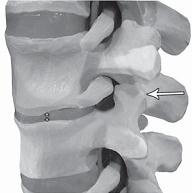

На фото № 12 макета позвоночника наблюдается перерастяжение дугоотростчатого сустава вследствие вытяжения, расширение фораминального отверстия, а также растяжение задних отделов фиброзного кольца межпозвонкового диска и сближение вентральных (передних) отделов тел позвонков. Это приводит межпозвонковый диск в клиновидное состояние, что способствует выталкиванию содержимого межпозвонкового диска из передних его отделов в задние.